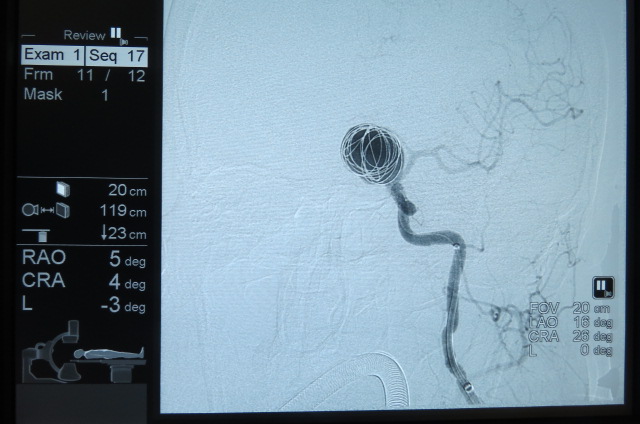

بیمار خانم 63 ساله می باشد به علت سرگیجه به بیمارستان مراجعه کرده است ، در MRI ضایعه بزرگ به اندازه 25MM گرد شبیه تومور مشاهده شده که در آنژیوگرافی مغزی ضایعه آنوریسم مغزی تشخیص داده شد،بیمار توسط تیم جراحی به سرپرستی دکتر کهنسال تحت جراحی بسته ( اینترونشن ) مغزی قرارگرفت و آنوریسم مغزی کاملا بسته شد و بیمار به بخش منتقل شد .

بر اساس گزارش به عمل آمده حال عمومی بیمار خوب می باشد . این عمل در شمال کشور و گلستان برای اولین بار انجام شد.